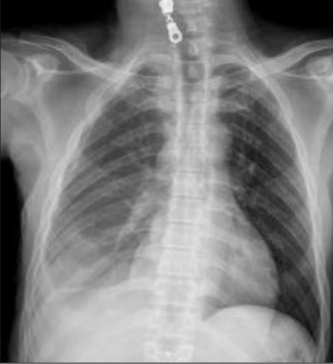

âȘ Table 5: We visualize samples of the generated reports for three cases. We bold the identical descriptions, underline the additional identified findings, and in red the failure findings..

X-ray Image | Baseline | M2TR | R2Gen | Ours |

![]() |

RĂ©gression du pneumothorax droit./Drain en place au niveau apical droit./OpacitĂ© en bande linĂ©aire au niveau du tiers infĂ©rieure de lâhĂ©michamp pulmonaire gauche./Scissurite droite./Silhouette cardiaque dâaspect normal./Absence dâanomalie du gril costal./ | StabilitĂ© du pneumothorax droit./Drain apical droit en place et fonctionnel./Bande opacifiante au niveau du tiers moyen de lâhĂ©michamp pulmonaire gauche./LĂ©gĂšre scissurite droite./ | Diminution du Pneumothorax gauche./Drain thoracique positionnĂ© Ă l'apex gauche./OpacitĂ© linĂ©aire sur le tiers supĂ©rieur de l'hĂ©michamp pulmonaire droit./ | RĂ©gression marquĂ©e du pneumothorax droit./Disposition dâun drain au niveau apical gauche./OpacitĂ© linĂ©aire dans le tiers infĂ©rieur de lâhĂ©michamp pulmonaire gauche./NormalitĂ© du gril costal et des parties molles./ |